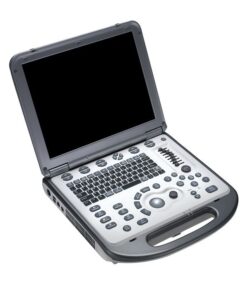

Mindray DP-10 – Diagnostic Ultrasound System

Mindray DP-10 is an ideal choice for B/W system, with the best-in-class combination of performance and ergonomic design.

Mindray DP-10 – Diagnostic Ultrasound System

Mindray DP 10 is an ideal choice for B/W system, with the best-in-class combination of performance and ergonomic design. Excellent image quality and PW Doppler imaging with auto measurement meet the requirements of different applications, helping you to enhance your diagnostic confidence. High definition LED with full screen design provides you with new operation experience.

Ergonomics

- Exceptional Ergonomic Design

- 12.1 inch high definition LED

- Full Screen design for easy cleaning

- 30 degree tilting angle adjustable monitor

- Maximum 2 universal transducer connectors

- User friendly control panel with backlit

- Light and compact design for extreme portability